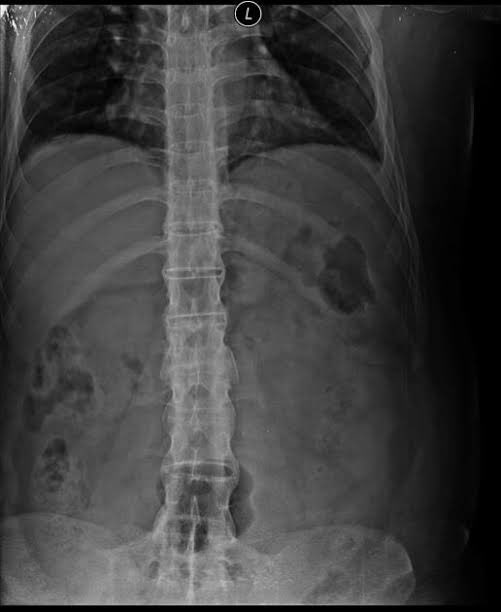

2️⃣ Bamboo Spine 🎋

🩻 Syndesmophyte fusion of vertebrae → straight, rigid spine

🟠 Seen in: Ankylosing spondylitis

📌 Look for squaring of vertebral bodies, sacroiliitis Image